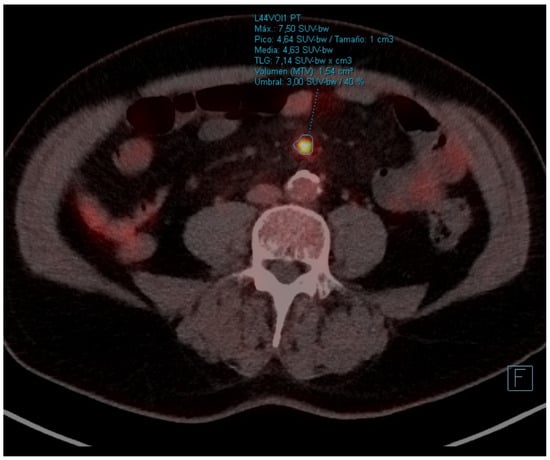

| PET-CT | April 2023 | Severe abdominal pain that had consulted 4 times in the emergency room | - Hypermetabolic persistence of adenopathies in the right cervical chain, lower paratracheal and right pulmonary hilum with dissociated response, some have progressed and others have improved. - Signs of mesenteric panniculitis, visualizing increased pseudonodular formations, several with FDG uptake up to SUVmax 7.50, not present in the previous study. |